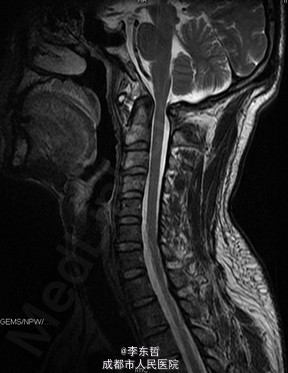

陈旧性寰枢关节脱位

患者男性,54岁,因“外伤后头颈部疼痛2年加重伴活动受限1个月”入院,自诉疼痛呈慢性起病,间歇性、反复发作并逐渐加重,为求进一步诊治故来我院,门诊以“陈旧性寰枢关节脱位”收入我科。